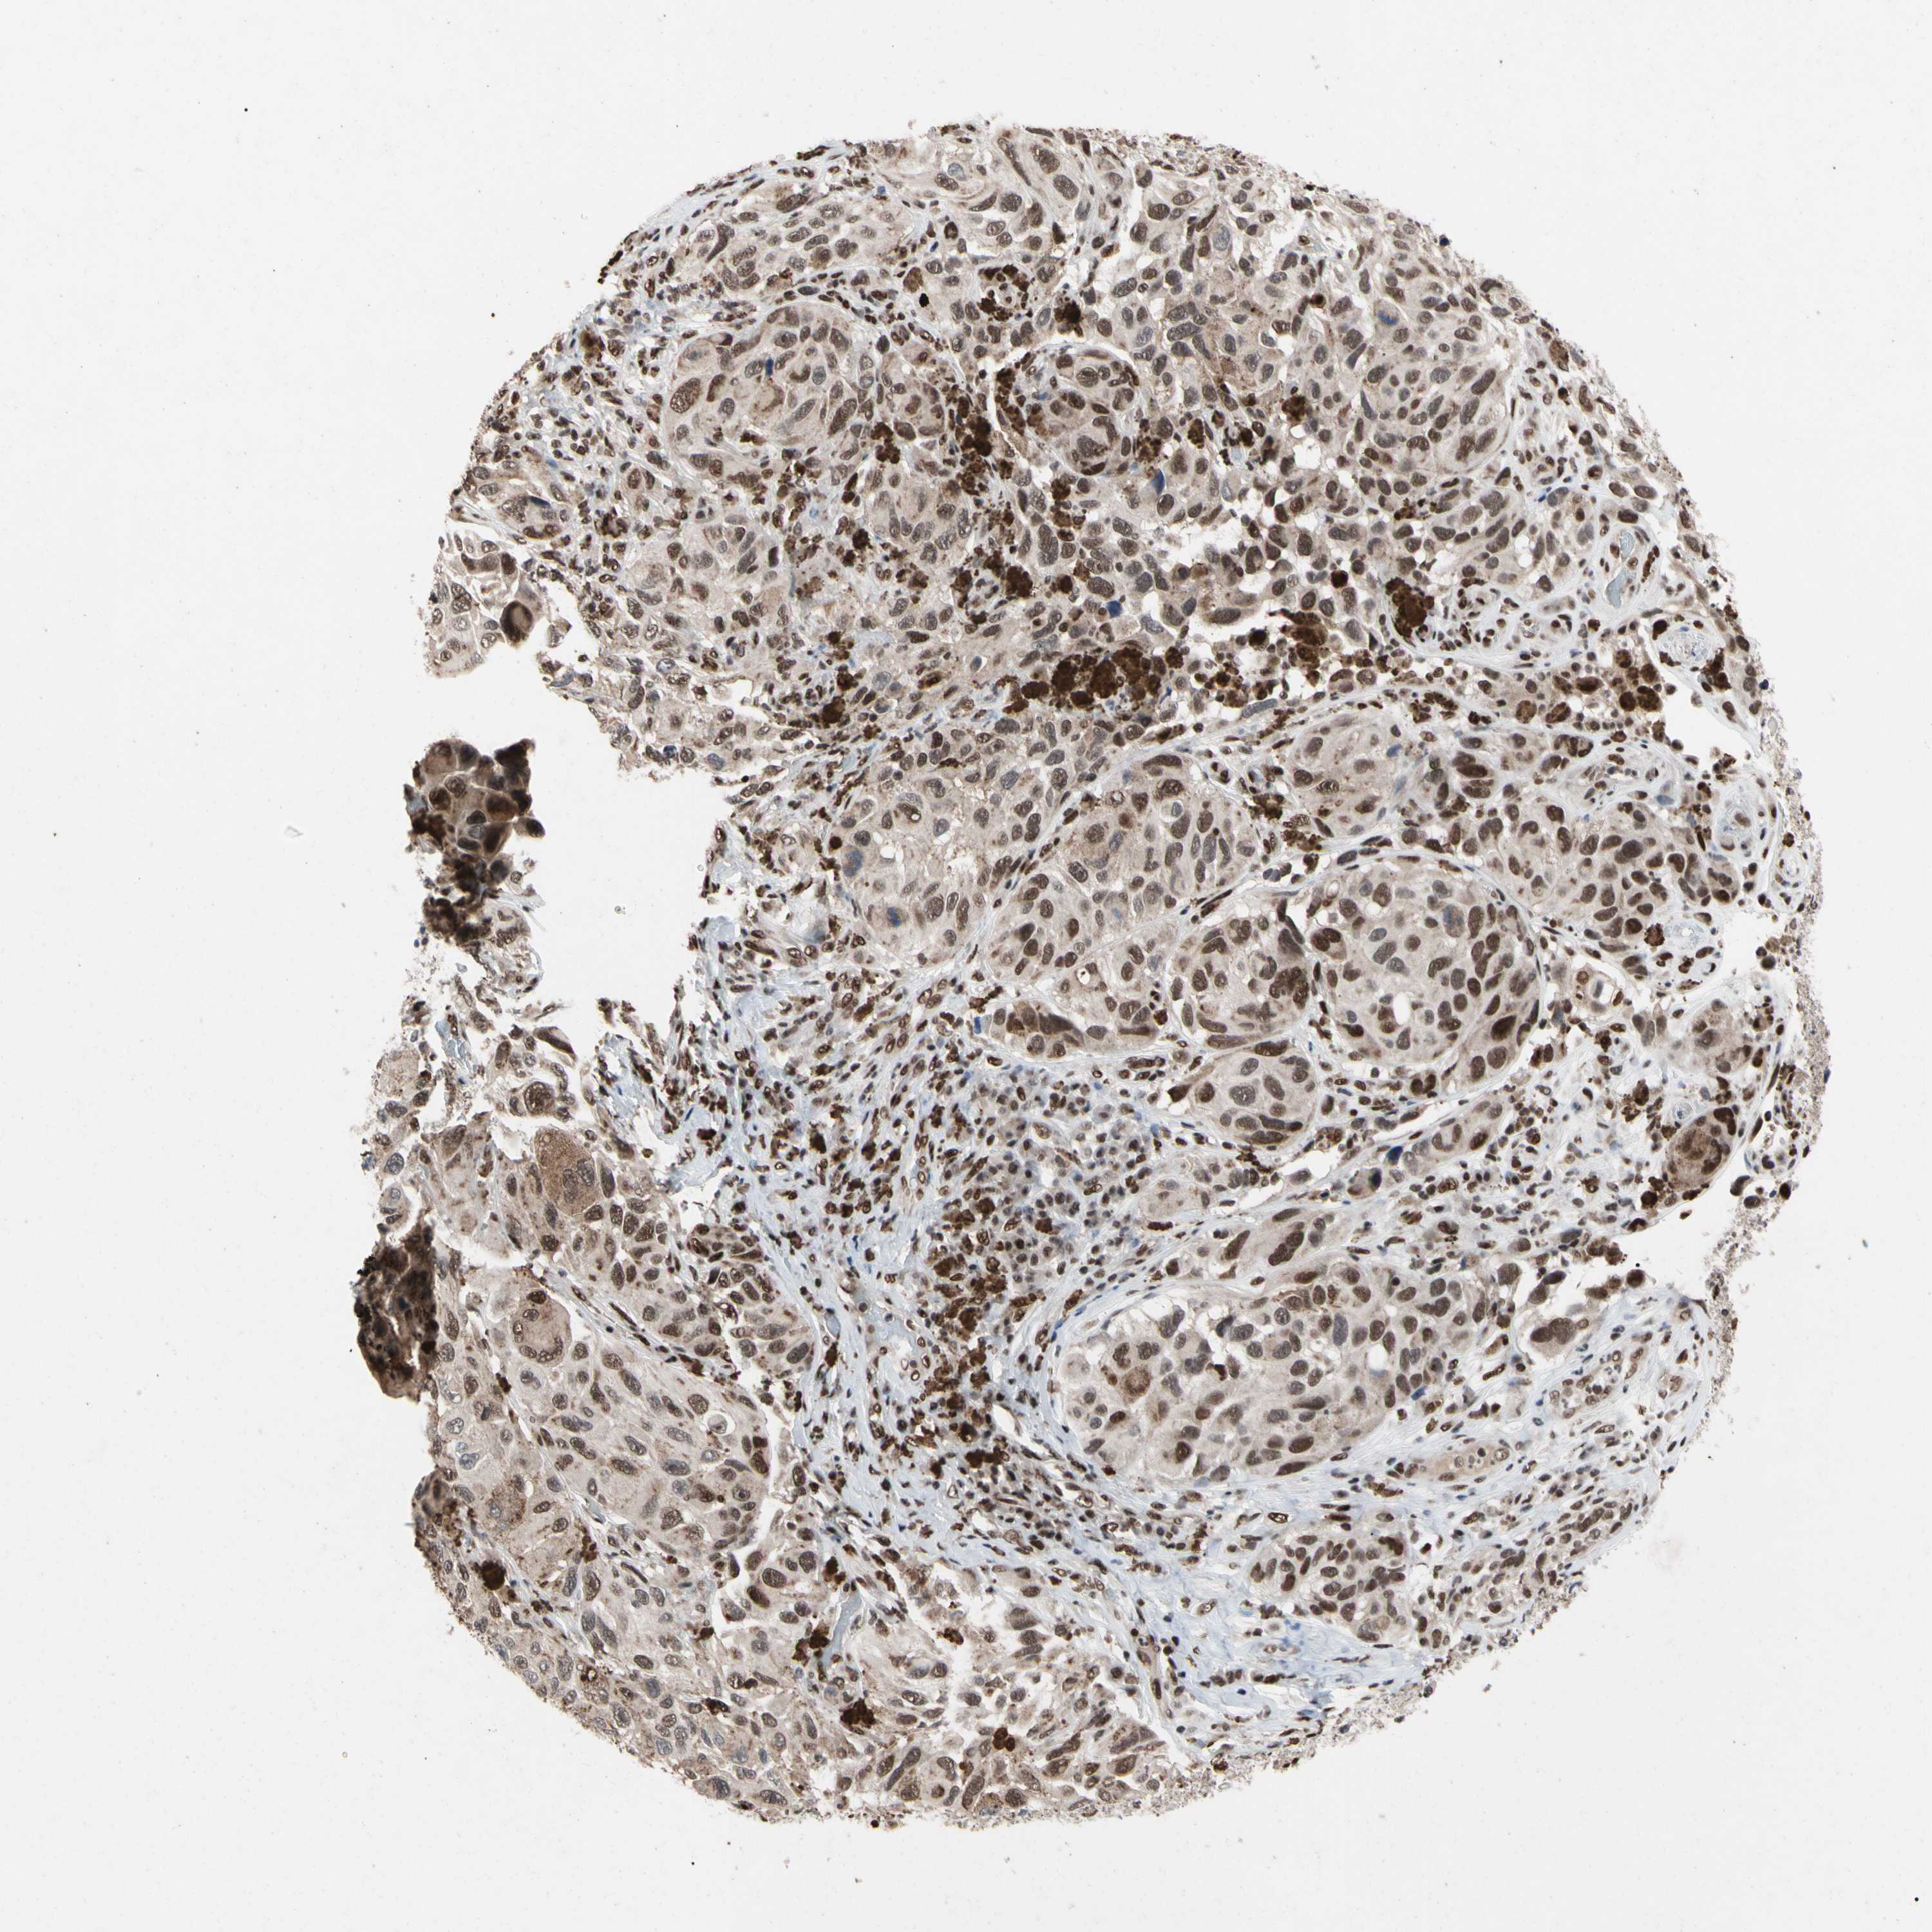

MELANOMA - Protein expressioni

A mouse-over function shows sample information and annotation data. Click on an image to view it in a full screen mode. Samples can be filtered based on level of antibody staining by selecting one or several of the following categories: high, medium, low and not detected. The assay and annotation is described here.

Note that samples used for immunohistochemistry by the Human Protein Atlas do not correspond to samples in the TCGA dataset.

Antibody stainingi

Antibody staining in the annotated cell types in the current human tissue is reported as not detected, low, medium, or high, based on conventional immunohistochemistry profiling in selected tissues. This score is based on the combination of the staining intensity and fraction of stained cells.

Each image is clickable and will lead to virtual microscopy that enables deeper exploration of all samples and also displays staining intensity scores, fraction scores and subcellular localization as well as patient and tissue information for each sample.

Antibody HPA008320

Antibody HPA008502

Staining

High

Medium

Low

Not detected

Intensity

Strong

Moderate

Weak

Negative

Quantity

>75%

75%-25%

<25%

None

Location

Nuclear

Cytoplasmic/membranous

Cytoplasmic/membranous,nuclear

Malignant melanoma, NOS

Malignant melanoma, Metastatic site